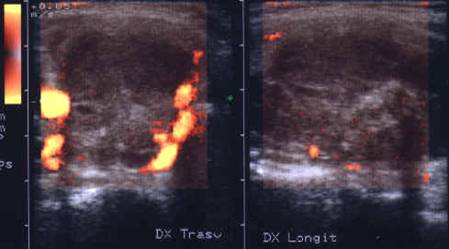

Lob drept , proiectie longitudinala si trasversala .

Barbat de 44 ani. Nodul mare in lobul drept si istm de 31x44x44mm, (30 cc) cu contur net, hipoecogen, neomogen, cu macrocalcificare.

Examn citologic: neoplazie oncocitara (a c. Hurthle).

Examen histologic postoperator: adenom cu celule Hurthle.